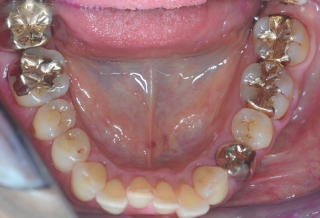

(図15)2015年7月27日、83歳。高年齢と残存歯数ばかりが問題視されているが、歯槽骨の状態、歯肉、Pocketの状態を含めた歯周病を評価すべきである

| EPP(mm) | 3 | 3 | 3 | 3 | 3 | 3 | 2 | 2 | 2 | 2 | 2 | 2 | 3 | 4 |

| MOBILITY | 0 | 0 | 0 | 0 | 0 | 0 | 0 | 0 | 0 | 0 | 0 | 0 | 0 | 0 |

歯周病治療38年経過:83歳(女性)残存歯数28本